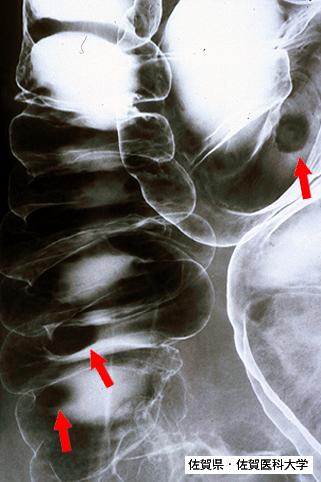

위와 대장에 다발병변을 보인 성인T세포 백혈병(ATL) (증례제시:사가의과대학、Dr.미즈구치)

Saga Pref., Saga Medical School (Saga Medical School)

악성 림프계종양 및 혈액계종양/ATL(성인 T세포백혈병)

대장/횡행

X-P

10~14

유(동시성)